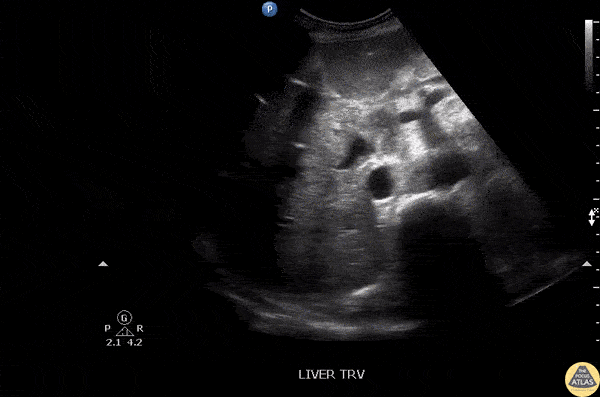

Biliary - Pneumobilia

Air can be noted within the biliary tract in this ultrasound of the RUQ. This patient was s/p Whipple procedure. Image courtesy of Robert Jones DO, FACEP @RJonesSonoEM Director, Emergency Ultrasound; MetroHealth Medical Center; Professor, Case Western Reserve Medical School, Cleveland, OH View his original post here